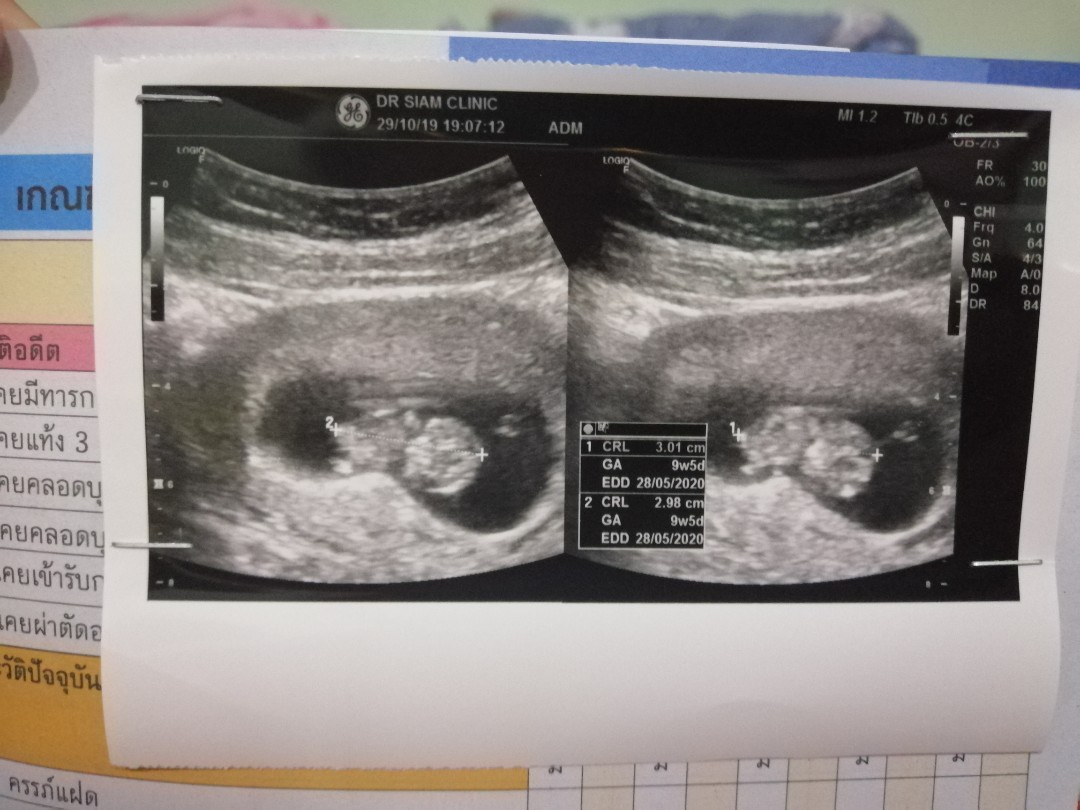

ของเรา 9wเห็นครบหมดนะค่ะ

10W เองค่ะเห้นหมดเลยค่ะ

บ้านนี้ 10weekเห็นครบจ้า